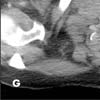

The lesion in the right supraclavicular region is visible on the superior aspect of the study (G, arrow). Images in lung windows, surprisingly, are unrevealing, as are images of the more cephalad aspects of the neck.

These images present a classic example of superior vena cava syndrome, with venous collaterals draining to the inferior vena cava. The differential diagnosis of the masses includes lung cancer with right supraclavicular metastatic disease, metastatic disease from another primary lesion, and lymphoma. Far less likely possibilities are infectious causes, such as tuberculosis and fungal diseases. A biopsy of the right supraclavicular mass reveals non–small-cell lung cancer.

Figure G